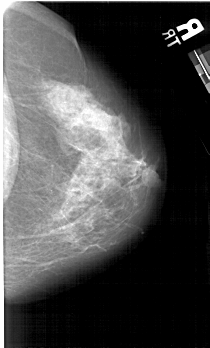

A_1631_1.LEFT_MLO

LEFT_MLO LINES 5491 PIXELS_PER_LINE 3331 BITS_PER_PIXEL 12 RESOLUTION 43.5 OVERLAY

FILE: A_1631_1.LEFT_MLO.OVERLAY

TOTAL_ABNORMALITIES 1

ABNORMALITY 1

LESION_TYPE CALCIFICATION TYPE PLEOMORPHIC DISTRIBUTION CLUSTERED

ASSESSMENT 4

SUBTLETY 2

PATHOLOGY BENIGN